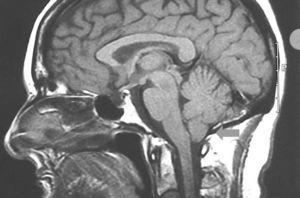

La malformación de Arnold-Chiari es una enfermedad neurológica de causa desconocida que se cree debida a un desarrollo insuficiente de la fosa craneal posterior, con la consiguiente expansión del cerebelo en dirección al canal raquídeo. Se han descrito cuatro variantes de la malformación, siendo el tipo I que presentamos la más frecuente de todas, caracterizándose por el desplazamiento caudal del cerebelo con herniación amigdalina por debajo del foramen magno y alargamiento en forma de cuña de las amígdalas. La malformación de Arnold-Chiari es más frecuente en mujeres (1:3) durante la quinta década de la vida. Su diagnóstico se basa en los hallazgos característicos, anteriormente descritos, de la resonancia magnética. Los síntomas más comunes son la cefalea occipital, que se desencadena con la maniobra de Valsalva o con la extensión del cuello, dolor retroorbitario y trastornos visuales o cuadros simulando enfermedad de Ménière con hipoacusia, vértigo y tinnitus5. A su vez, la compresión del tronco encefálico puede dar lugar a hidrocefalia o siringomielia hasta en un 40 % de los casos6.

Presentamos el caso de una paciente de 54 años de edad con antecedentes de talasemia minor, intervenida de hernia discal L5-S1 y de un tumor óseo parietal derecho en 2000 del cual no aportaba informes. Fue diagnosticada de síndrome de Klippel-Trénaunay, tras valoración dermatológica, en 2003 ante la presencia de una malformación vascular tipo nevus flammeus en la extremidad inferior izquierda de límites bien definidos y geográficos, junto con venas varicosas en su interior que le conferían una tonalidad eritematoviolácea, todo ello acompañado de un alargamiento llamativo de dicha extremidad (figs. 1 y 2). Con posterioridad precisó valoración neurológica por un cuadro de inestabilidad y de giro de objetos de varios meses de evolución. En la exploración neurológica presentaba un signo de Romberg con caída a la derecha y marcha inestable a la deambulación. Se solicitaron pruebas de imagen donde se objetivó la presencia de un descenso de las amígdalas cerebelosas en el interior del foramen occipital compatible con malformación de Arnold-Chiari tipo I (fig. 3).

Figura 3.Herniación amigdalina por debajo del foramen magno.